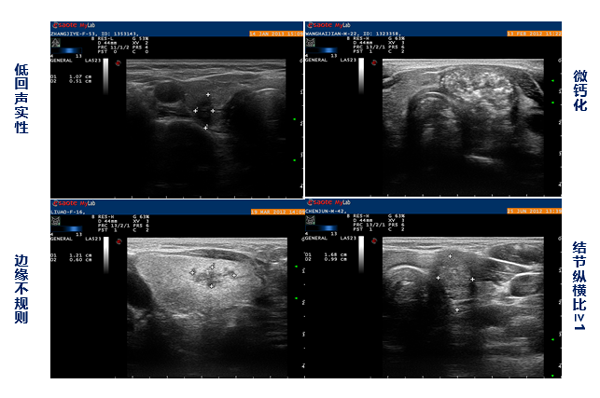

另外,恶性结节的超声特点主要包括以下方面:

1. 低回声或极低回声;

2. 边缘不规则、模糊或外侵;

3. 结节内多发点状钙化;

4. 结节呈垂直性生长-纵横比大于1;

5. 淋巴结皮髓结构不清,门结构消失,出现液化、囊性变或多发钙化等。(图1:甲状腺结节超声恶性征象)